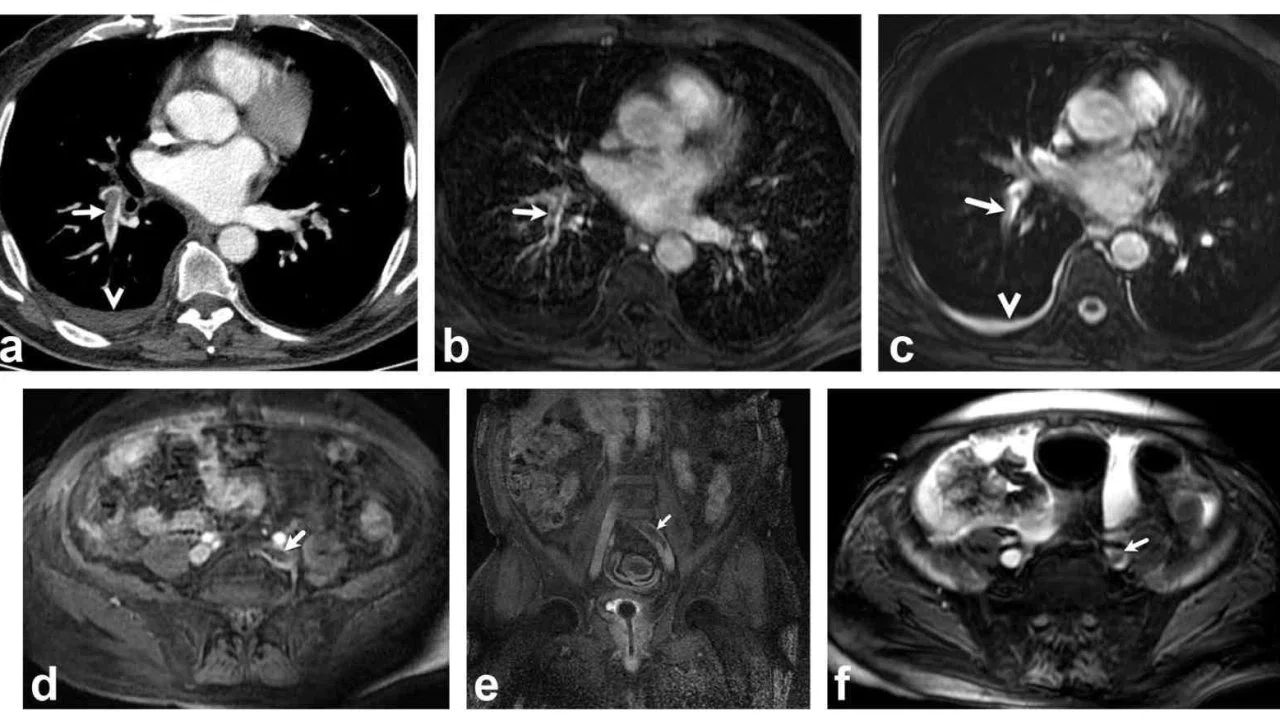

Bir dönem Denizli Tekden Hastanesinde de çalışan ve çalışmalarına ABD’de devam Dr. Nevzat Karabulut ve ekibinin yaptığı, British Journal of Radiology dergisinde yayımlanan "Diagnostic performance of contrast-enhanced and unenhanced combined pulmonary artery MRI and magnetic resonance venography techniques in the diagnosis of venous thromboembolism" başlıklı araştırmada manyetik rezonans (MR) yöntemi kullanılarak hem akciğer damarlarının hem de pıhtının kaynağı olan bacak toplardamarlarının aynı anda, tek bir incelemede değerlendirilebileceği gösterildi. Toplam 44 hastanın incelendiği çalışmada elde edilen sonuçlar oldukça dikkat çekti.

Kontrastlı MR yöntemi, hastaların tamamında akciğer embolisini doğru şekilde tespit ederken; kontrastsız MR yöntemi de yüksek doğruluk oranına ulaştı ve önemli ölçüde güvenilir sonuçlar verdi. Bu bulgular, radyasyon içermeyen MR yönteminin pıhtı hastalığını saptamada güçlü bir alternatif olduğunu ortaya koydu. Özellikle Radyasyon riskinin daha önemli olduğugenç hastalarda ve gebelerde MR’ın güvenli ve etkili bir seçenek olabileceği vurgulandı.